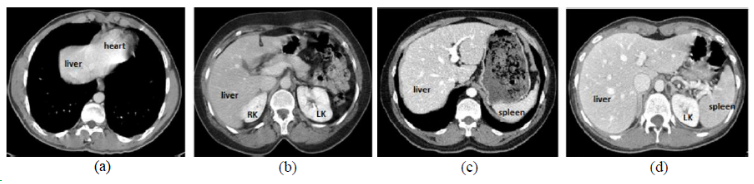

CHAOS

| CHAOS | 肝/肾/脾 | 分割 | CT+MRI | 40CT+120MRI | 0/1标签 | dcm |

CHAOS是一个多脏器,多模态分割数据集。